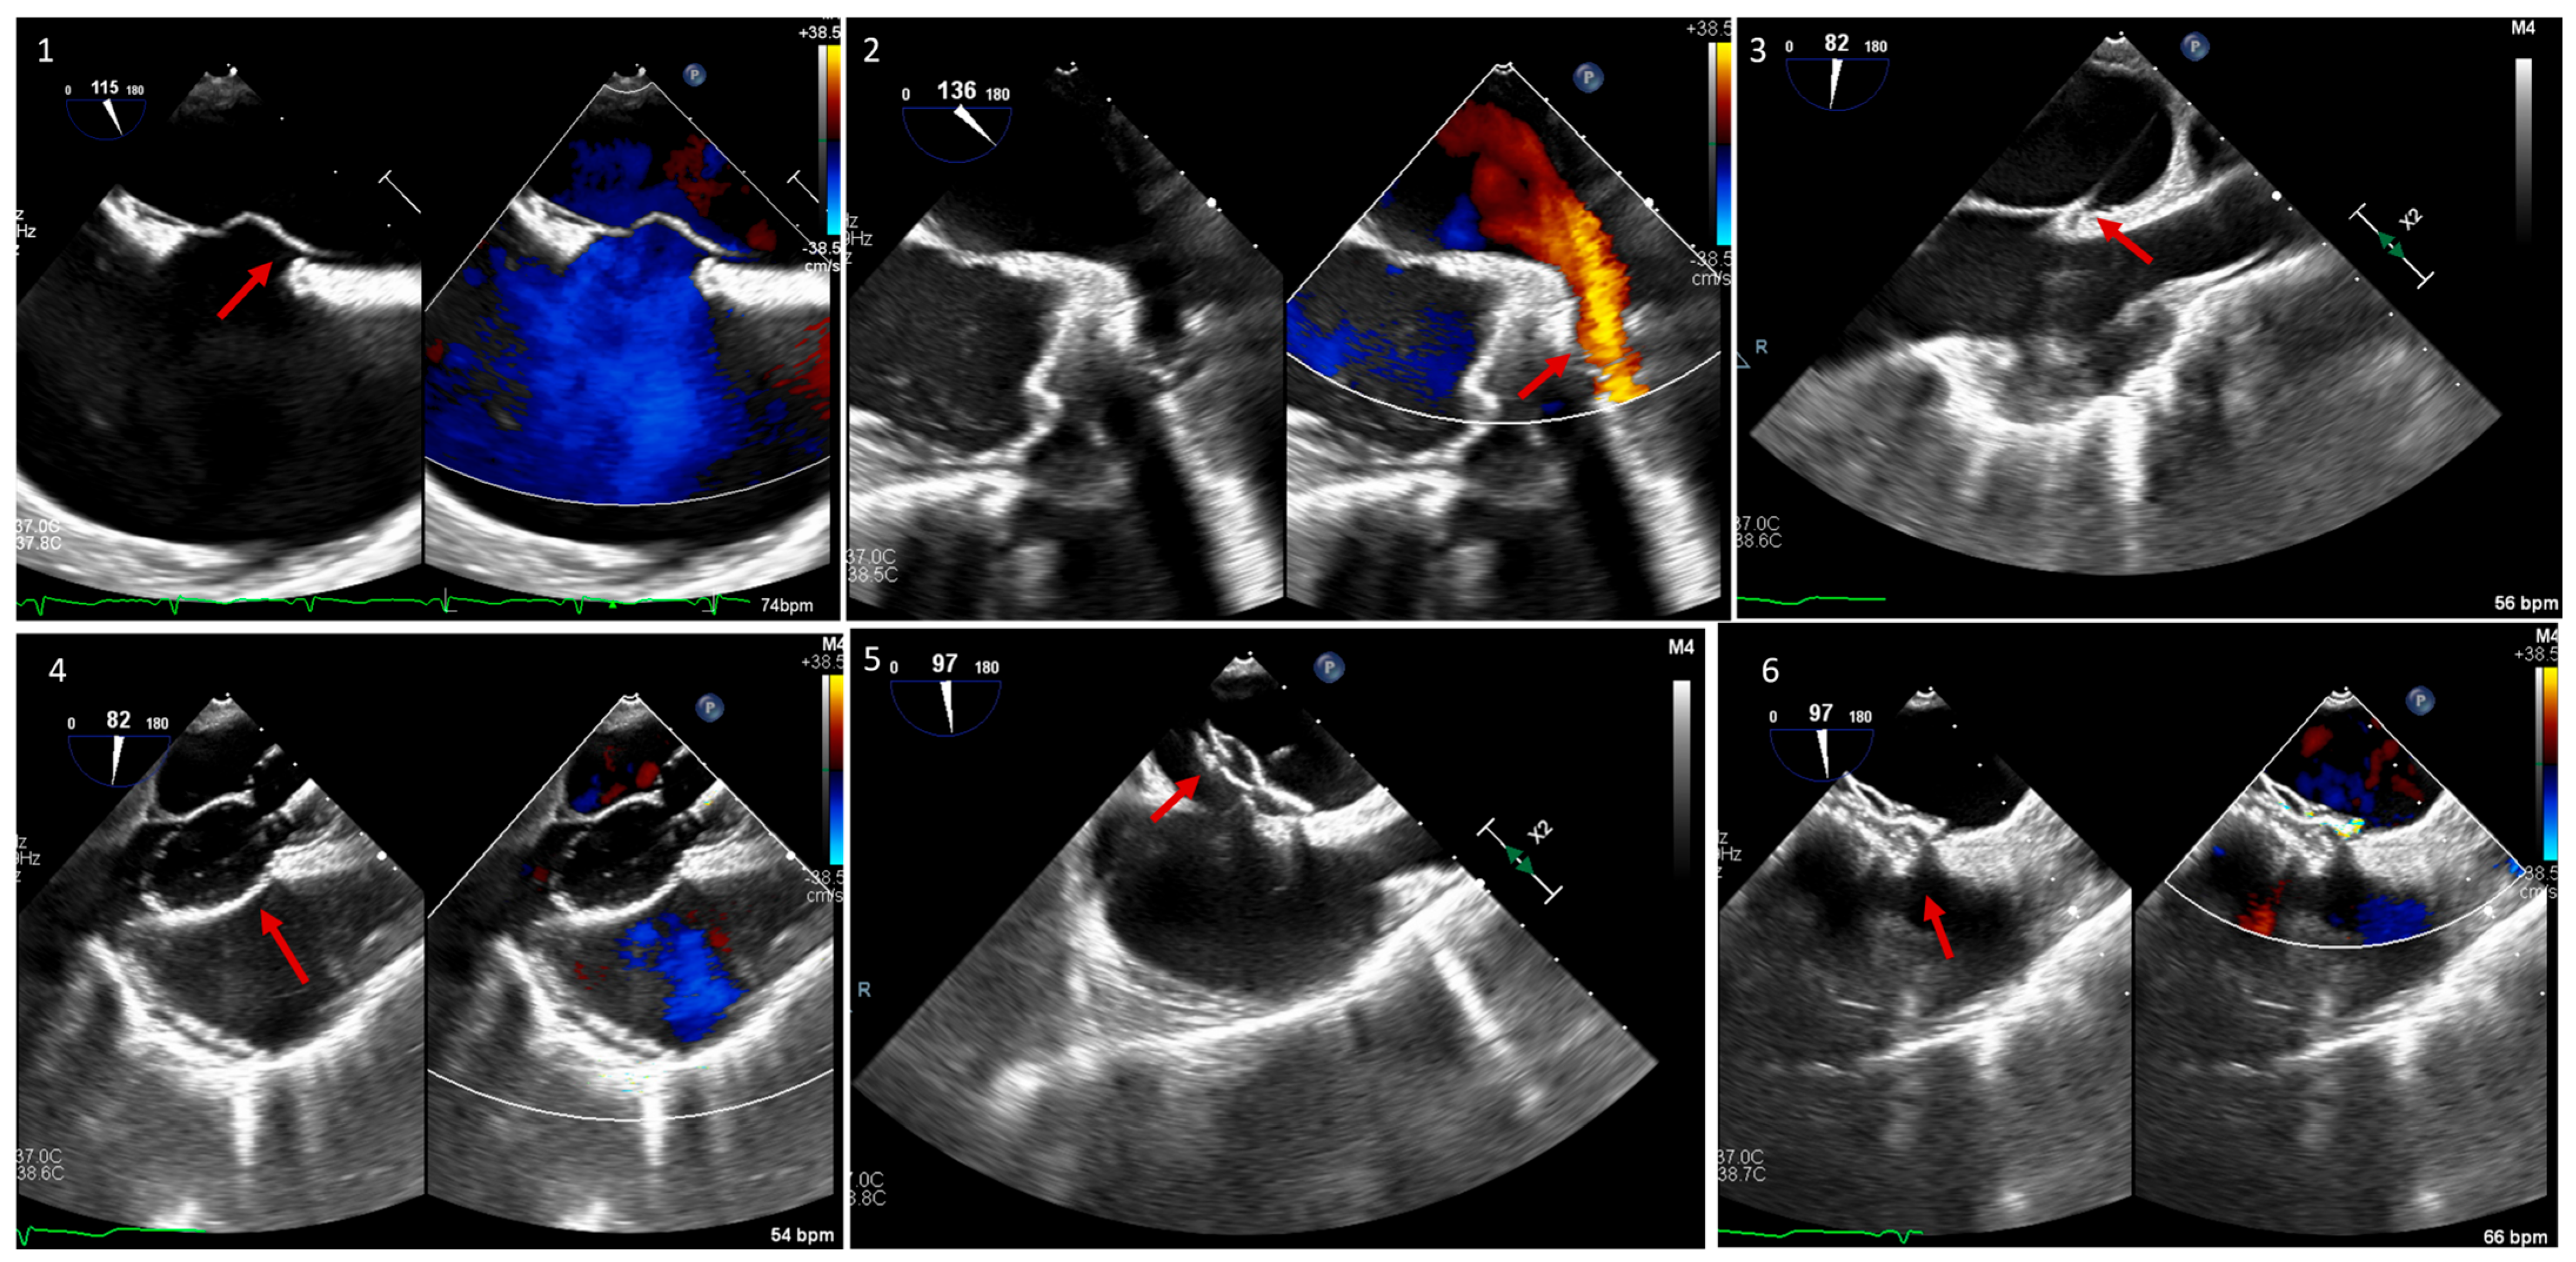

5. Paravalvular Leak Intervention